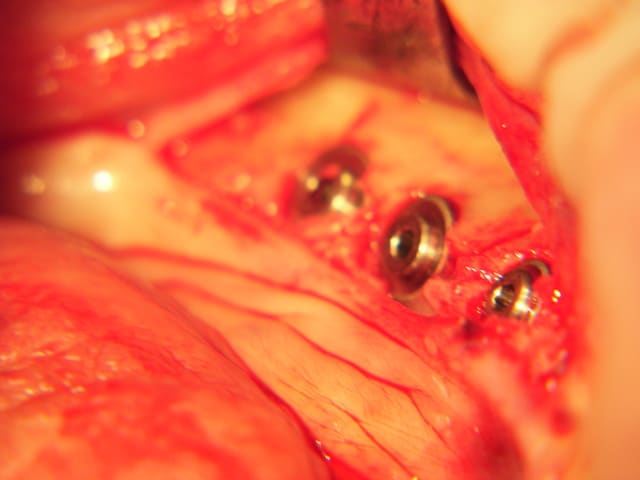

la suite

combiné de mini expansion et classique implants courts 8 et 6 mm 4 et 4,6 de diam.

fente verticale, decharges latérales expanseurs, forets pour finir, implants lisse et pose de 3 Axioms